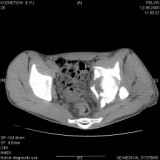

Уважаемые коллеги! Хотелось бы услышать совет по тактике лечения представлленого больного.Поступил после лечения в одном изотделений области. Травма 2,5 месяца назад. После выведенияиз шока был произведен остеосинтез перелома бедра, предплечья, до перевода к нам проводилосьвытяжение по оси шейки бедра за стержень, введенный в большой вертел. На сегодня деформацияригидна, клинически мобильности не определяется. Заранее признателен. P.S. Данный вид травм не включен в перечень "высокотехнологичных операций", направить длялечения по квотам Минздрава очень сложно.

Все-таки надо бы начать не с КТ, а с обзорного снимка таза и косых проекций впадины.

Это обзорные и косые снимки

С уважением,

Привет, Леонид. Оскольчатый высокий двухколонный перелом в такие сроки трогать не надо, т.к. это про такие переломы сказано: "кто с ножом на Ж. пойдет тот в ней и останется...".